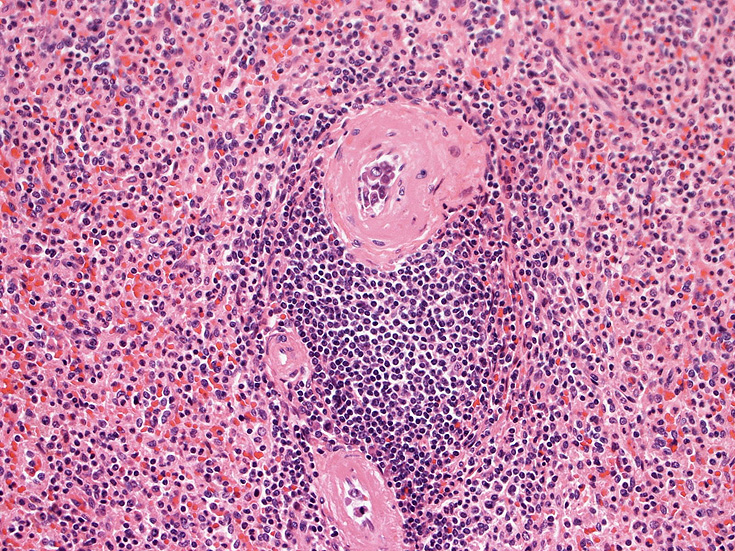

骨髄の組織所見

肺組織所見